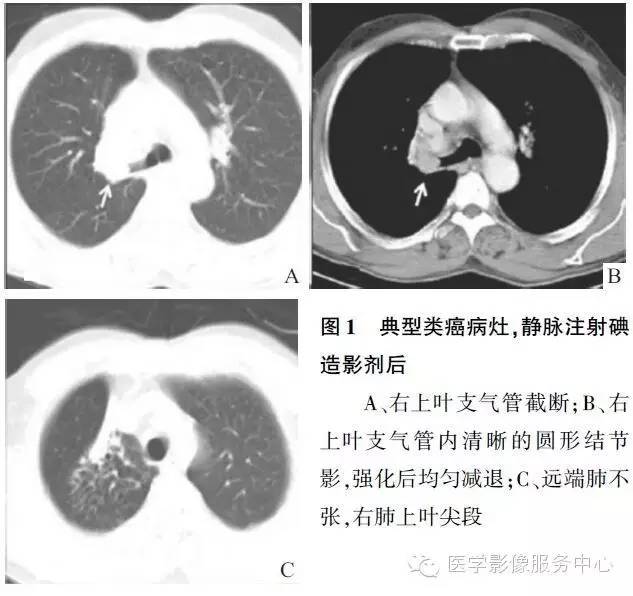

1.典型类癌

(1)中心型肿瘤发生于主支气管、叶、段支气管,生长缓慢,形成腔内息肉样结节或肿块,边缘光滑,可同时向腔外浸润。平片可表现正常,或有阻塞性肺炎及阻塞性肺不张。支气管造影可见腔内边缘光滑的充盈缺损。CT平扫多见腔内生长的、边缘光滑、清晰的肿块,可有钙化,直径多在1~2cm,团注增强后呈明显强化。可伴有阻塞性肺炎及不张,纵隔及肺门淋巴结肿大很少见。对位于肺中带的病灶,CT上难以与血管结构区分,可行MRI检查,T2wI上病灶呈高信号强度,血管则为低信号。